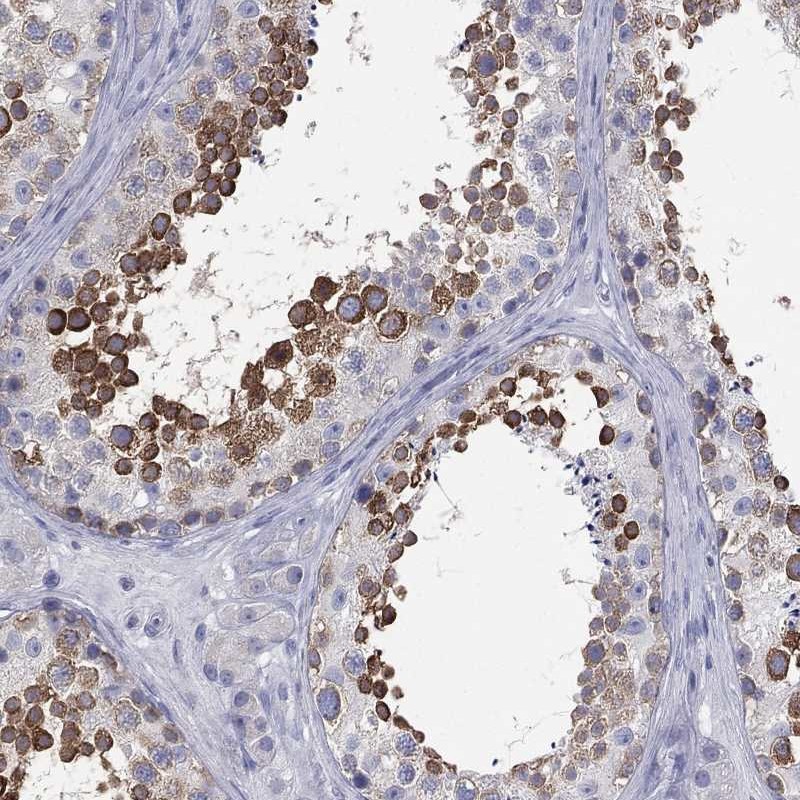

Immunohistochemical staining of human testis shows strong cytoplasmic positivity in cells in seminiferous ducts.